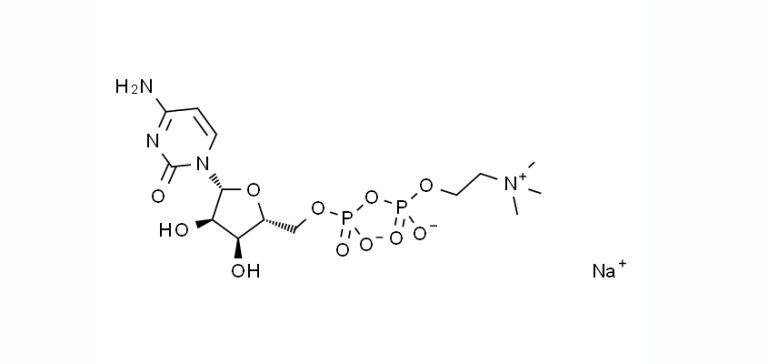

Citicoline sodium (also known as CDP-choline) is a compound that plays a…

Citicoline sodium (also known as CDP-choline) is a compound that plays a…

Citicoline sodium, also known as CDP-choline (cytidine 5′-diphosphocholine), is a compound that…

Citicoline sodium (also known as CDP-choline sodium or cytidine diphosphate choline sodium)…

Citicoline Sodium, also known as CDP-Choline (cytidine diphosphate choline), is a nootropic…

Citicoline sodium (also known as sodium cytidine 5′-diphosphocholine or CDP-choline) is a…

Citicoline Sodium, also known as cytidine diphosphate-choline (CDP-choline), is a compound that…